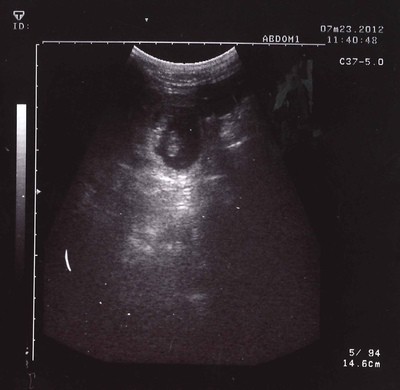

22. července 2012 - Aileenka dnes absolvovala kontrolní sonografii, v bříšku pan doktor viděl 5, možná 6 štěňátek.

Brzy se tedy dočkáme dalších chlupáčků a Bastien s Verunkou svých psích vnoučátek. ![]()

Vrh C očekáváme v druhé polovině srpna,

již nyní se na nás mohou obracet zájemci o štěňátka.